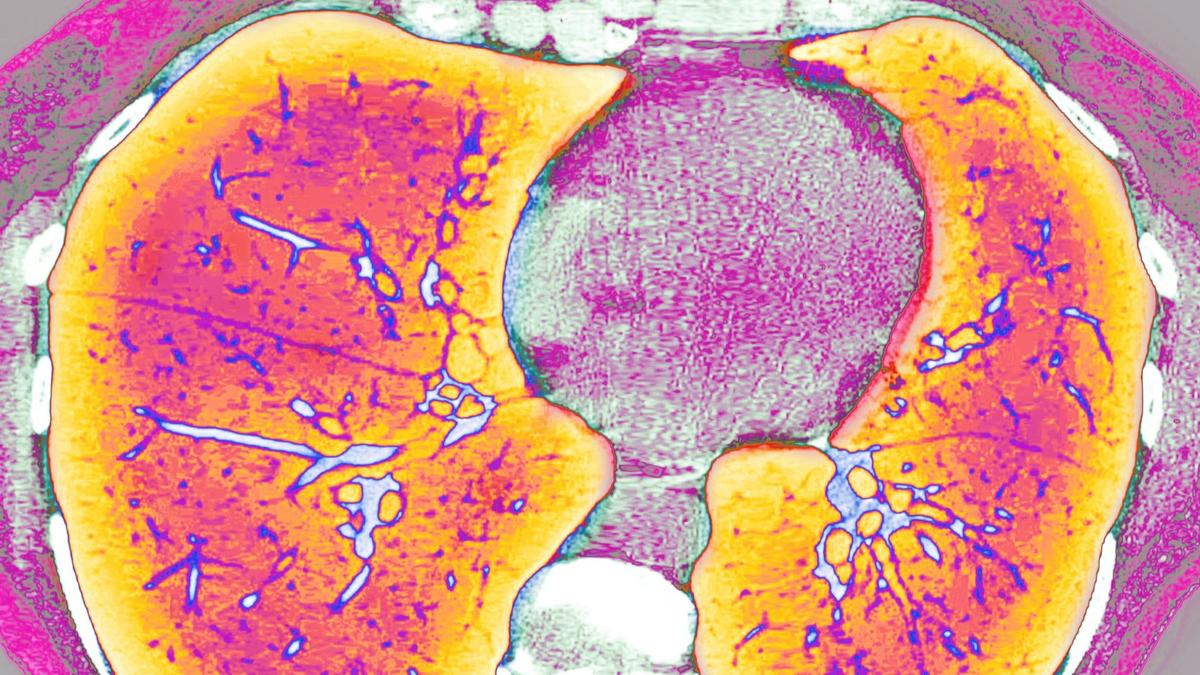

Куда уходит фарма Российские пациенты с муковисцидозом жалуются, что в стране пропал жизненно важный препарат «Пульмозим». Компания-производитель отрицает, что это из-за войны и санкций